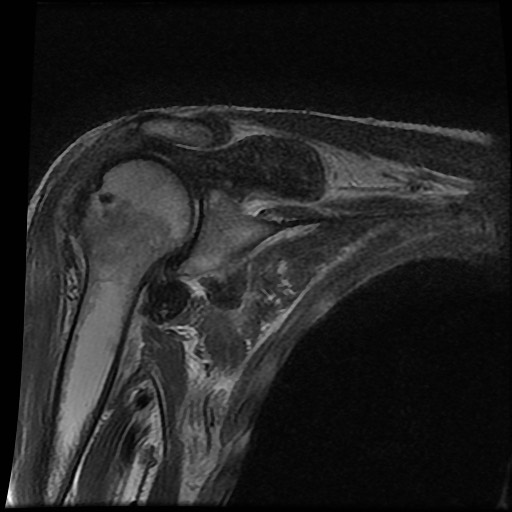

Tiếp tục xem hình ảnh MRI của bệnh nhân này.

Hình ảnh MRI:

Tràn dịch lan tỏa tất cả các khớp cổ tay.

Phù tủy xương lan tỏa tất cả các xương cổ tay.

Bào mòn xương, ví dụ tại xương thuyền, xương đầu và xương móc.

Phá hủy khe khớp và sụn khớp, rõ nhất tại khớp STT và CMC4/5.